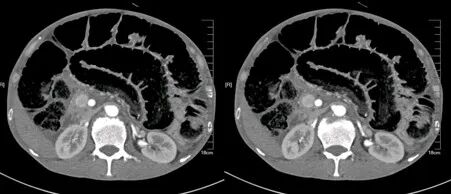

肾挫伤

肾挫伤是一种比较多见的肾损伤,肾组织损伤较轻,肾包膜和肾盂大多保持完整,肾实质内产生瘀血或血肿,并有少量血液流入肾盂导致血尿。肾挫伤在X线造影片上可不显示形态上的改变。一般均能自行愈合而不造成严重后果。